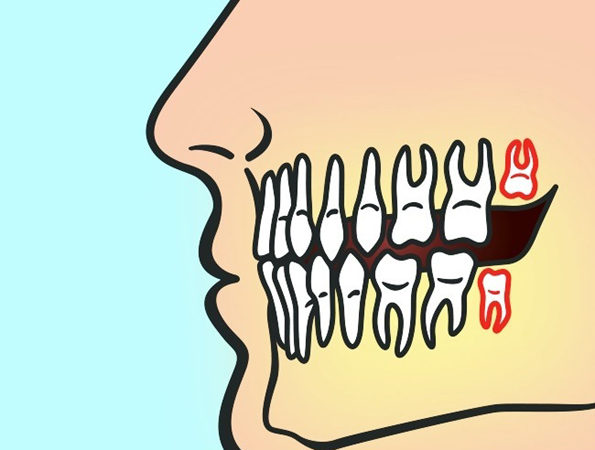

- Ако забите се целосно скриени под непцето, но не можат да излезат. Во овој случај, тие можат да формираат циста која ќе ги уништи корените на соседните заби.

- Ако забите не се пораснати целосно. Во тој случај, ќе имате проблем околу одржувањето на хигиената и како резултат ќе дојде до насобирање на бактерии што може да предизвика голем број забни заболувања.

- Ако нема доволно простор за забите, умниците можат да им наштетат на соседните заби.